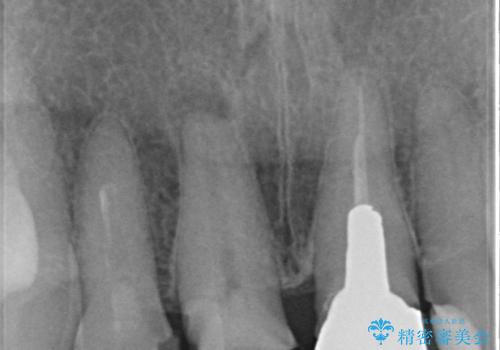

結婚式に合わせて根管治療からのやりかえを短期集中治療で計4回で終える計画を立てます。

セラミック治療は外から見えるのはクラウンの色味・形態、歯肉の状態のみですが、X線撮影において現れるクラウンと歯牙の適合や、ファイバーコアの精度・根管充填の密度に、より長い予後を達成するための要素が含まれると考えます。